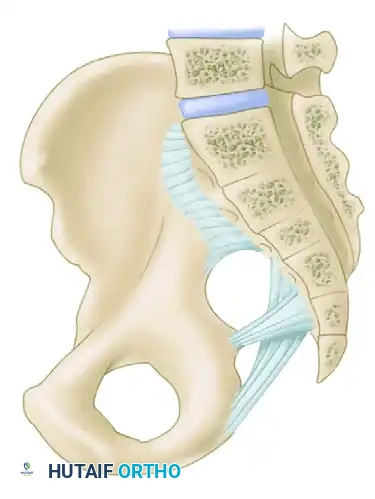

A profound understanding of pelvic osteoligamentous anatomy is the foundation of both classification and treatment. The pelvis is a ring structure composed anteriorly of the pubic and ischial rami connected at the symphysis pubis. A fibrocartilaginous disc separates the two pubic bodies, providing a degree of physiologic elasticity.

Posteriorly, the sacrum and the two innominate bones are joined at the sacroiliac (SI) joints. The SI joint itself possesses no inherent bony stability; its integrity relies entirely on a massive, complex ligamentous network.

The Posterior Tension Band

The posterior ligamentous complex is the primary weight-bearing and stabilizing structure of the pelvis. Tile famously compared the relationship of the posterior pelvic ligamentous and bony structures to a suspension bridge, with the sacrum suspended securely between the two posterior superior iliac spines.

The critical ligaments include:

* Interosseous Sacroiliac Ligaments: The strongest ligaments in the body, forming the primary restraint to vertical shear forces.

* Anterior and Posterior Sacroiliac Ligaments: Provide rotational stability to the SI joint.

* Sacrotuberous Ligaments: Resist rotation in the sagittal plane (flexion of the sacrum).

* Sacrospinous Ligaments: The primary restraints to external rotation of the hemipelvis.

* Iliolumbar Ligaments: Connect the L5 transverse process to the iliac crest, augmenting vertical and rotational stability.

Biomechanical Restraints

Pelvic stability is determined by these ligamentous structures acting across various planes. The primary restraints to external rotation (the "open book" deformity) are the ligaments of the symphysis, the sacrospinous ligament, and the anterior sacroiliac ligament. Vertical displacement of the hemipelvis is controlled by all the aforementioned structures. However, if the anterior structures are disrupted, vertical stability may still be maintained by intact interosseous sacroiliac, posterior sacroiliac, and iliolumbar ligaments.

Surgical Warning: A rotationally unstable hemipelvis may remain vertically stable due to an intact posterior tension band. Recognizing this distinction is paramount, as it dictates whether the patient requires simple anterior stabilization or complex posterior ring reconstruction.

Vascular Anatomy

The internal iliac plexus of arteries and veins lies in intimate proximity to the anterior sacrum and sacroiliac joints. Disruption of the posterior ring frequently tears the thin-walled presacral venous plexus, leading to massive retroperitoneal hemorrhage. Arterial bleeding, typically from the superior gluteal or internal pudendal arteries, occurs in approximately 10-15% of hemodynamically unstable patients and requires emergent angioembolization.